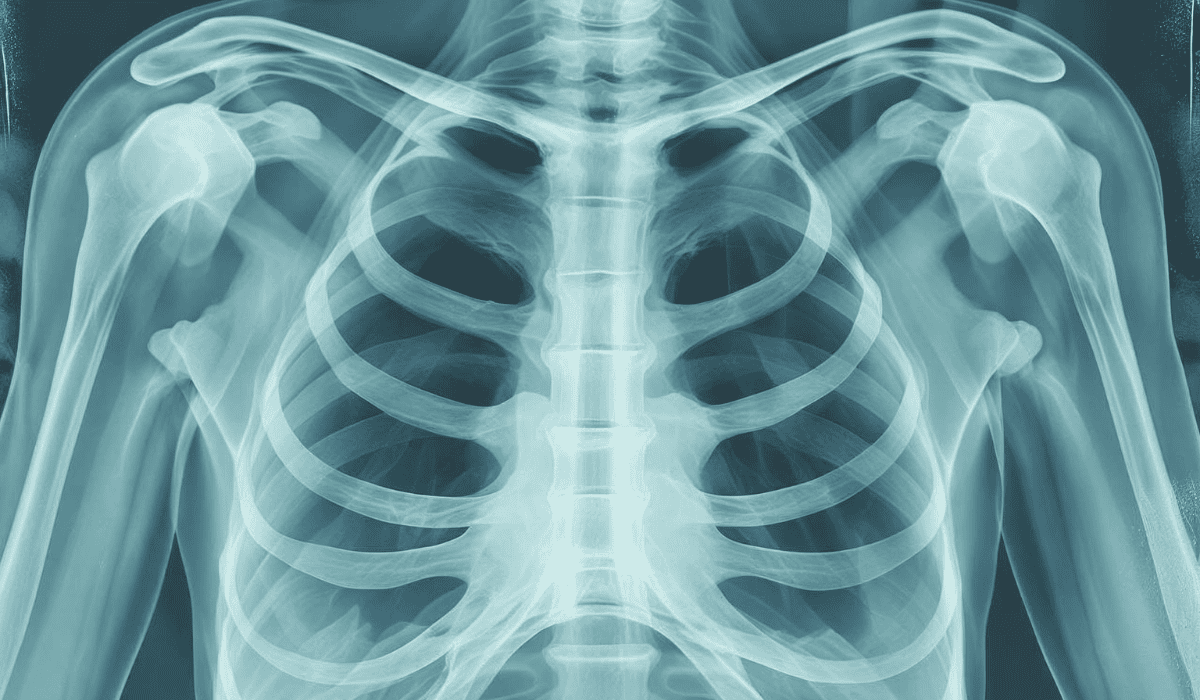

Rak płuca to złośliwy nowotwór wywodzący się z komórek nabłonka wyściełającego drogi oddechowe. Dzieli się go na dwa główne typy: drobnokomórkowy (około 15–20 proc. przypadków) i niedrobnokomórkowy (około 80–85 proc.). Ten drugi rośnie zwykle wolniej, co daje większą szansę na leczenie, ale i on często zostaje wykryty zbyt późno.

W miarę rozwoju raka płuca guz może blokować drogi oddechowe, zmniejszać powierzchnię wymiany gazowej lub powodować wysięk w opłucnej. W efekcie pacjent odczuwa narastające trudności z oddychaniem, nawet przy niewielkim wysiłku. Objaw ten bywa też błędnie przypisywany astmie, POChP czy anemii.

Pacjenci często są przekonani, że mają problemy z kręgosłupem lub mięśniami, zwłaszcza jeśli ból nasila się przy ruchu. Tymczasem może to być wynik ucisku guza na nerwy lub ścianę klatki piersiowej. Jeżeli ból utrzymuje się dłużej niż kilka tygodni – nawet bez innych objawów – należy wykonać RTG lub tomografię klatki piersiowej.

Lekarze podkreślają, że jeśli infekcje wracają mimo leczenia antybiotykami lub dotyczą tej samej części płuca, konieczna jest dalsza diagnostyka. Tomografia komputerowa może wówczas wykazać obecność zmiany nowotworowej, która była niewidoczna w zwykłym zdjęciu rentgenowskim.